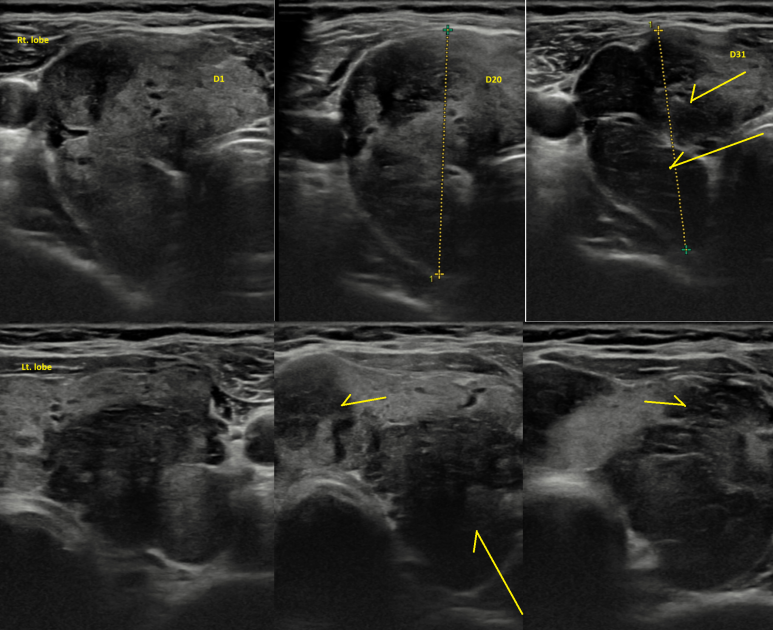

60대 초반 남자, 초진 4일전에 미끄러지고 넘어졌다. 앉아있다 일어나면 어지럽고.. 주변이 돈다 (현훈, whirling을 기술). 1분정도.. 하루에 4~5회 정도 구역감/구토 (-) 특이한 과거력; 구강암 (설암) 수술 - **대학병원 2018 과거 흡연자 음주; 약 1년전까지 3~4/wk*3병 기술하는 어지러움의 양상 (현훈) 이나 증상기간을 보았을 때 이석증이 의심되는데... Dix-hallpike test에서 양측 양성, 안진의 발생과 같은 양상의 어지러움이 유발된다. (안진의 up-beating은 뚜렷해 보이지 않았다. frenzel 안경을 이용하여 검사한 것도 아니고...) Benign Paroxysmal Positional Vertigo (BPPV) Diagnosis and Treatment | Ento Key ; 양측 epley 를 한 방향씩 시행함 양측에 발생한 경우를 처음보았고 따라서, 에플리 시행 이후 다시 di